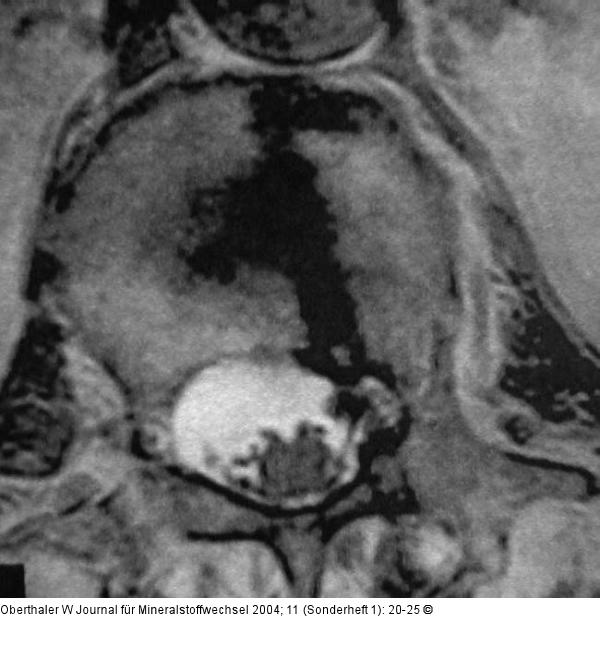

Abbildung 10: Kyphoplastie Perforation nach medial ohne klinische Symptome, die zufällig später festgestellt wurde |

Abbildung 10: Kyphoplastie

Perforation nach medial ohne klinische Symptome, die zufällig später festgestellt wurde |